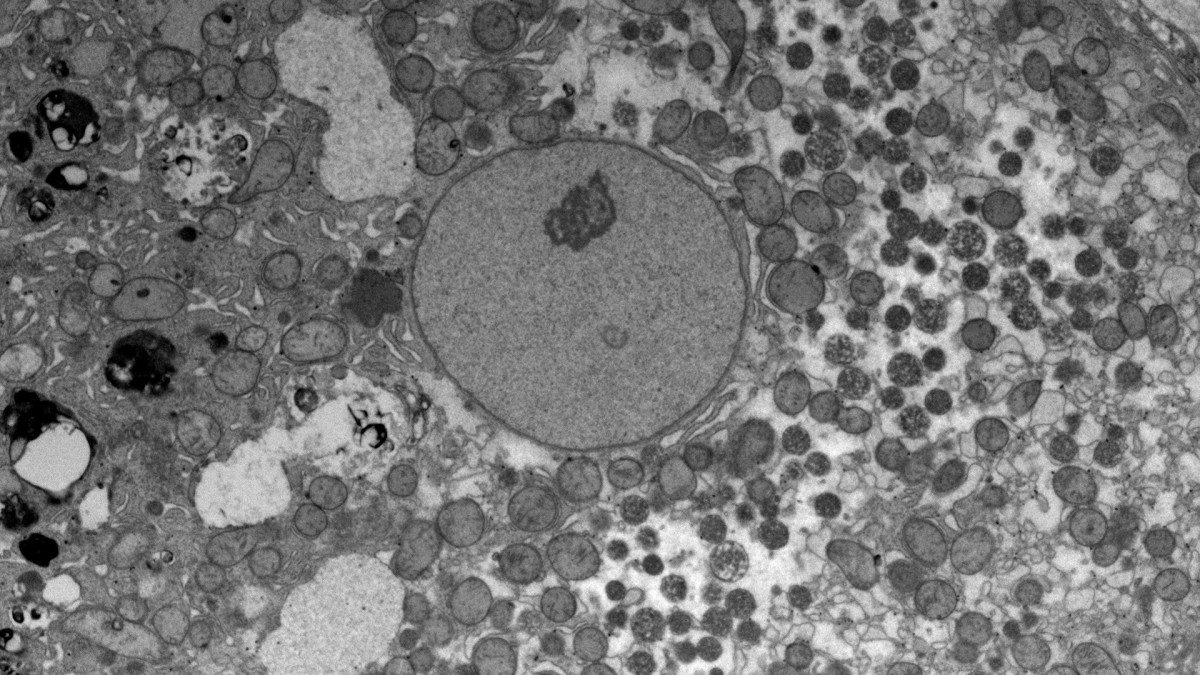

This suite houses the scanning and transmission electron microscopes in addition to equipment required for sample preparing and processing